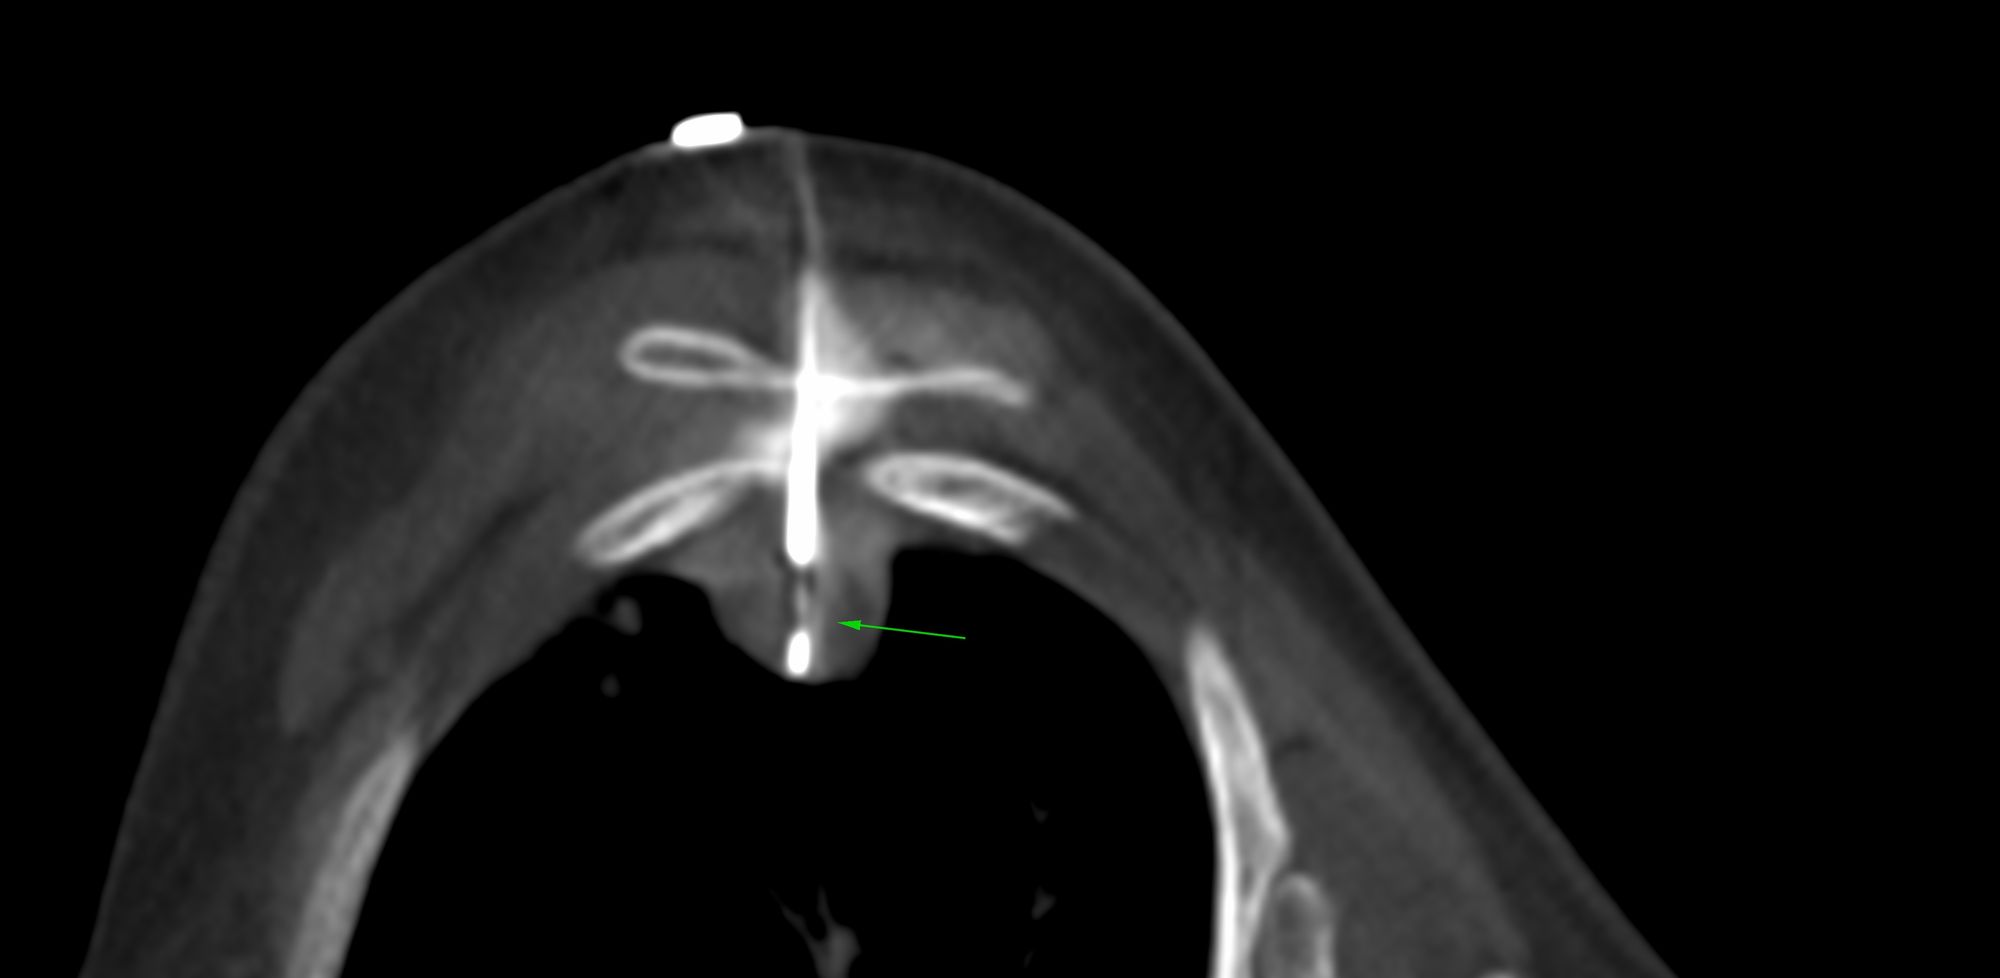

Case 40: Radiofrequency Ablation (RFA) of D10 Pars Osteoid Osteoma

Bhavin Jankharia - 05 June 2021